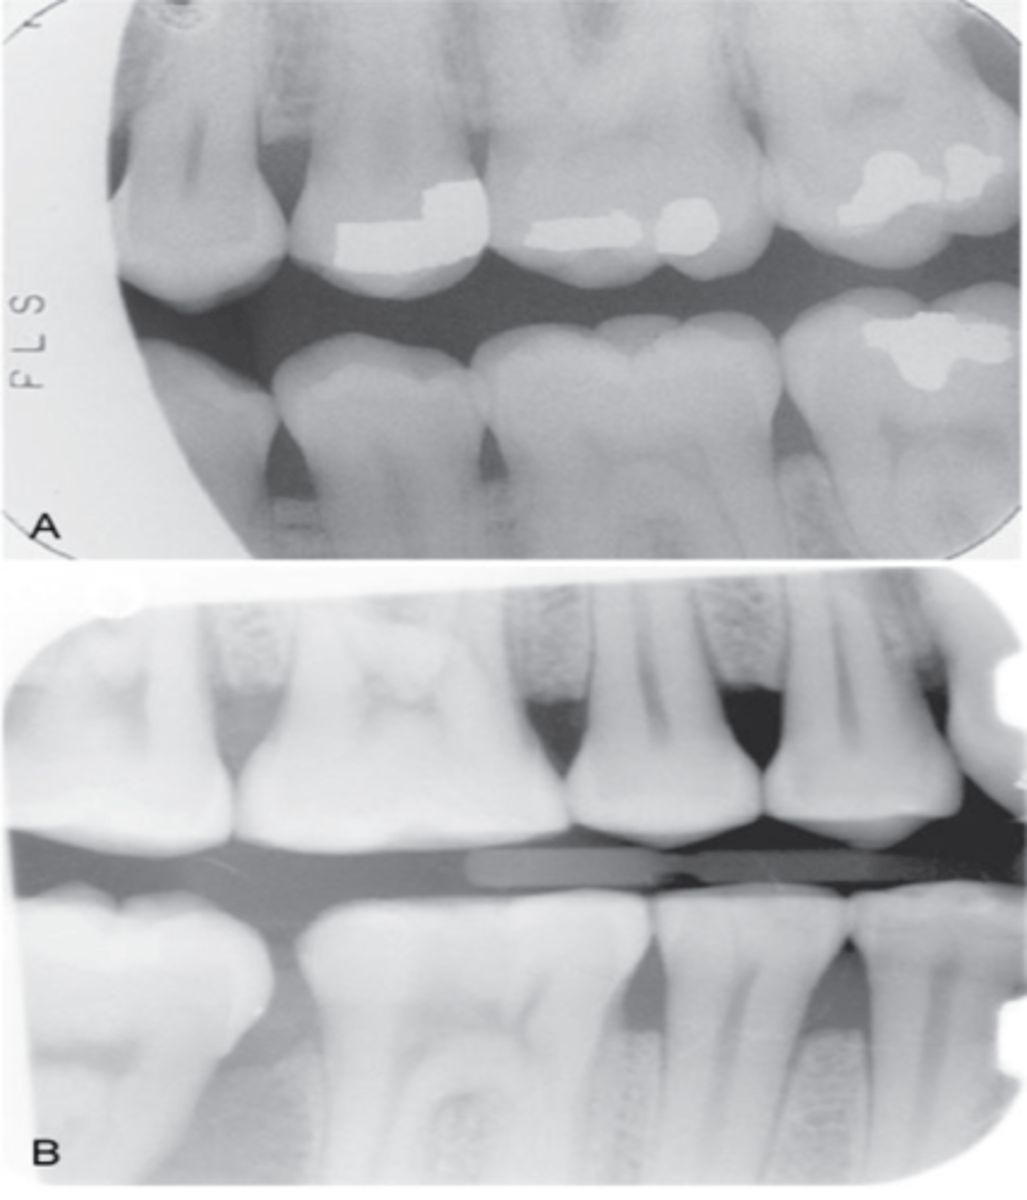

incorrect placement of premolar bite wing

distal surfaces of the canine are not visible of the image

receptor too far back

make sure anterior edge of receptor is at the midline of the mandibular canine

incorrect placement of molar bite wing

third molar regions not visible on the image

receptor too far forward

make sure anterior edge of the receptor is at the midline of the mandibular second premolar

center the molar bite wing over the mandibular second molar

distorted image

incorrect vertical angulation

vertical angle was negative

use +10 degree angle when using bite tab